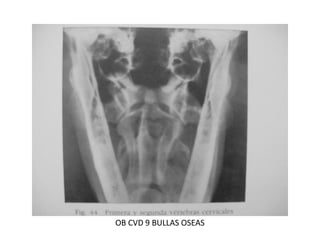

OB CVD 9 BULLAS OSEAS